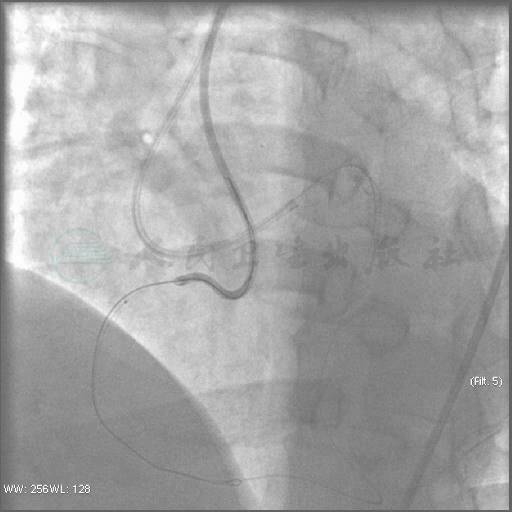

穿刺右股动脉,置入7F动脉鞘,7F AL1.0指引导管送至右冠口,在130cm Finecross微导管支撑下,先后使用Pilot 50(2根)、Pilot 150、Miracle 3(2根)、Conquest Pro导丝以及平行导丝技术均未能通过右冠远段闭塞处至血管真腔,遂放弃进一步正向PCI治疗(图4~图7)。

图4 导丝在微导管支撑下不能通过病变到达真腔

图5 采用双导丝技术

图6 平行导丝技术

图7 仍然无法到达右冠远端真腔,遂放弃